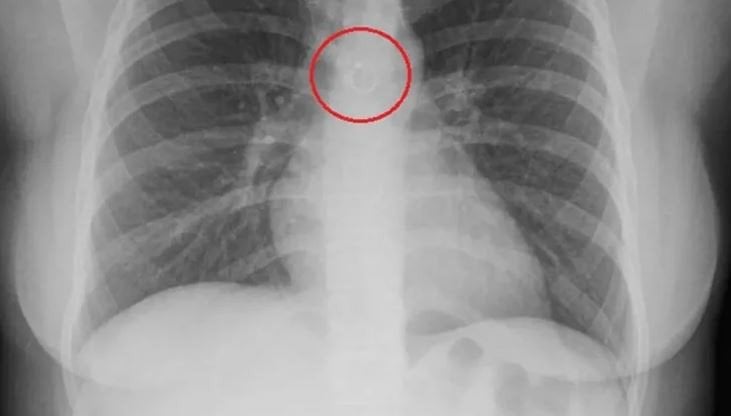

Моніка Деяніра Кабрера Барахас протягом приблизно місяця не могла позбутися кашлю, який не давав їй спокою. Зрештою вона вирішила звернутися до лікаря та пройти обстеження. Жінка очікувала, що рентген покаже якусь типову проблему, однак результат виявився зовсім несподіваним — на знімку вона побачила власний пірсинг.

Пірсинг в легенях / © скриншот з відео

Згодом здивування змінилося серйозним занепокоєнням, коли лікарі повідомили, що металева прикраса знаходиться всього за 0,5 міліметра від аорти. Через це жінці призначили термінову операцію. Процедура, яка мала тривати близько 20 хвилин, виявилася значно складнішою і затягнулася майже на півтори години, але завершилася невдачею.